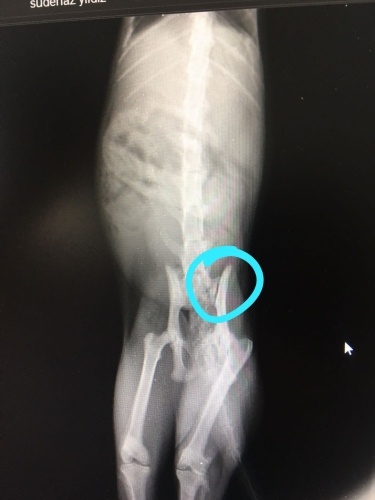

Ayağı kalçadan kırılmış sokak keisine evde bakım veriyoruz şuan."Hareketini kısıtlayın zamanla iyileşir" dedi iki veteriner. Ek olarak da Felaxa malt vermişler kardeşime. Üzerinde hem "tüy yumağı önleyici" hem de kas kemik destekleyici yazıyor.Ilk defa duyduğumuz bir ürün bu.Duyan kullanan var mı? Biz ona kemik suyu vermeye başladık.Bu maltın bir faydası olur mu? Aşina olan kullanan var mı?